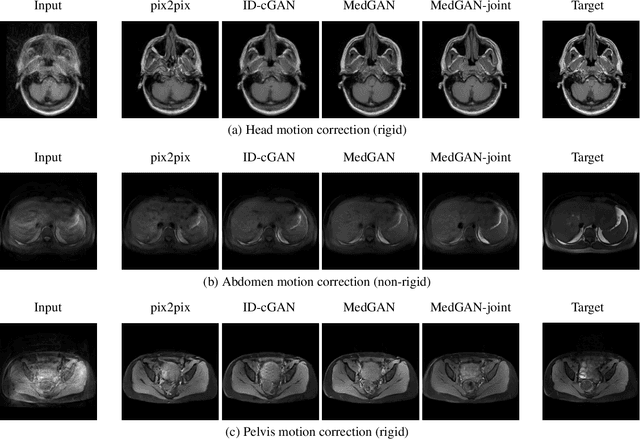

Motion artifacts are a primary source of magnetic resonance (MR) image quality deterioration with strong repercussions on diagnostic performance. Currently, MR motion correction is carried out either prospectively, with the help of motion tracking systems, or retrospectively by mainly utilizing computationally expensive iterative algorithms. In this paper, we utilize a new adversarial framework, titled MedGAN, for the joint retrospective correction of rigid and non-rigid motion artifacts in different body regions and without the need for a reference image. MedGAN utilizes a unique combination of non-adversarial losses and a new generator architecture to capture the textures and fine-detailed structures of the desired artifact-free MR images. Quantitative and qualitative comparisons with other adversarial techniques have illustrated the proposed model performance.